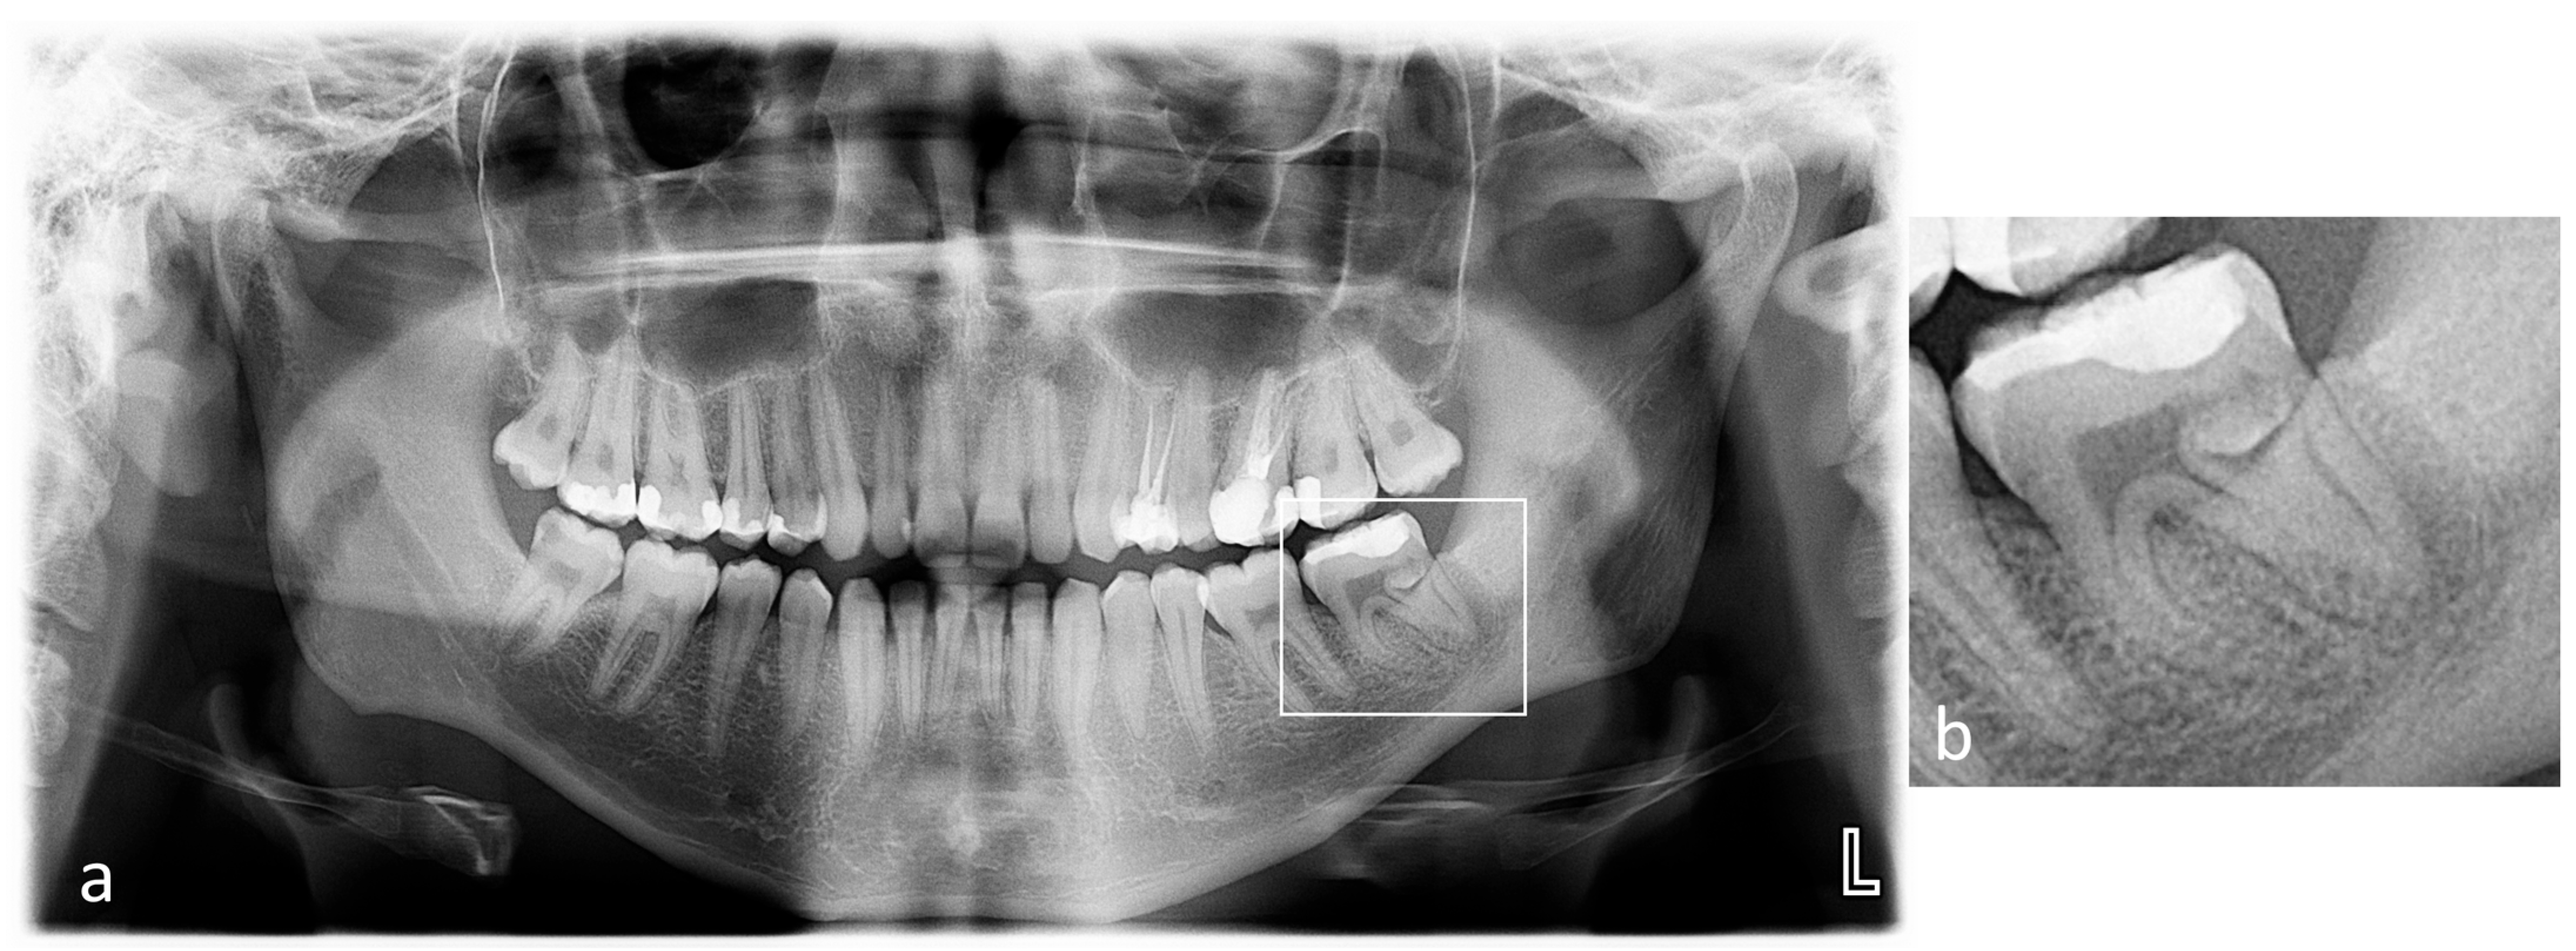

2. Case Presentation

2.1. The First Visit